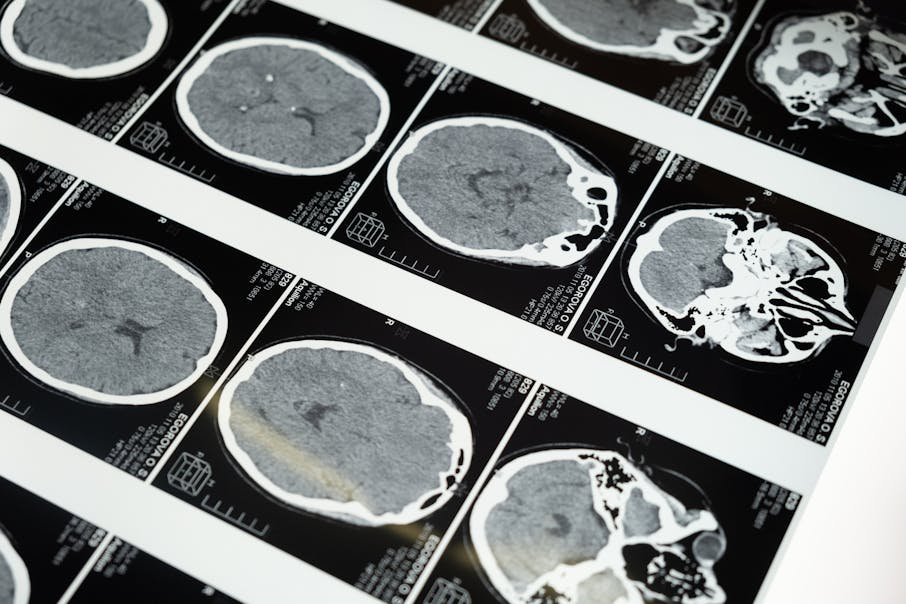

6 Best Open Source DICOM Annotation Tools

In this article, we will cover several of the most popular open-source tools for DICOM annotation 9 that our team often discusses with leaders from Data Operations and Machine Learning teams (as well as radiologists and clinicians), including the key use cases, benefits, and downsides of these tools – we will also look ahead to what’s next after getting started with these tools, and considerations that teams make as they go forward in their data annotation journey.

Viewing and annotating medical data, images, and videos is a crucial, and frequent, task for many practitioners in the healthcare industry. This is especially true as AI becomes more prominent across different fields of medicine. The AI in healthcare market is expected to grow from $11 billion in 2021 to $188 billion by 2030, which greatly increases the demand for high-quality medical data. (Source: Statista)

A starting point for many when evaluating how to go about this task, will be to start with open-source medical imaging annotation tools – these tools are a popular choice in the medical sector and can be a smart way to save money when getting started on an image or video dataset annotation project.